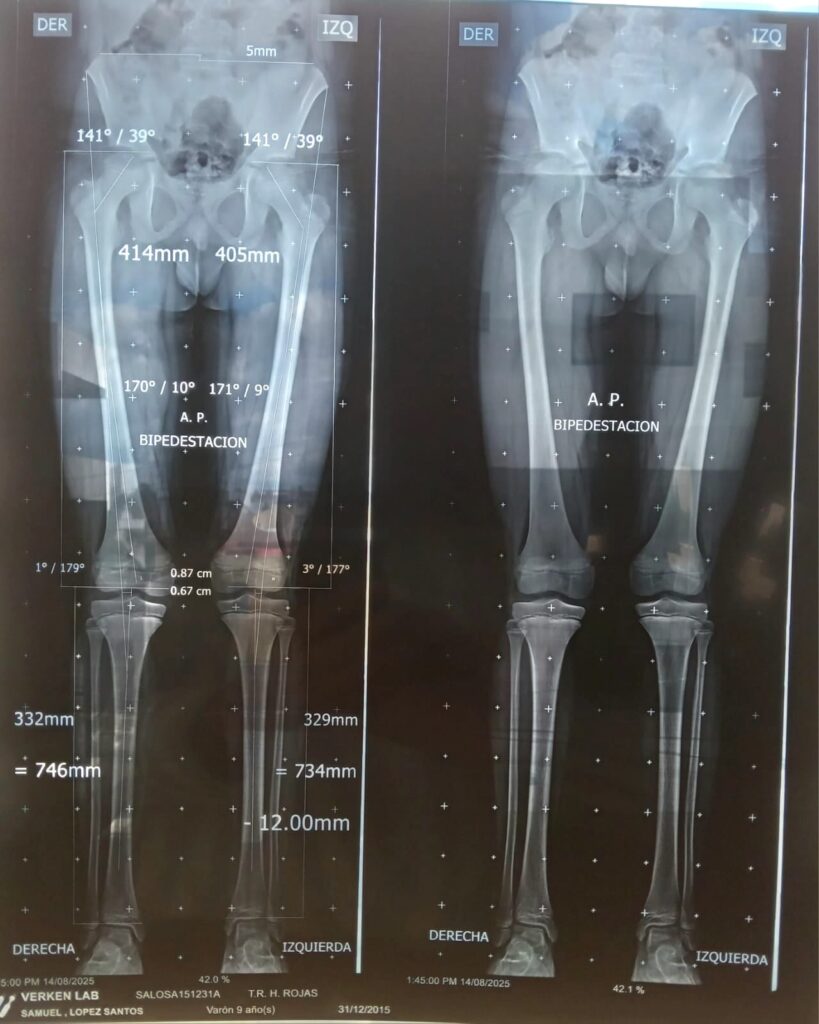

Despu茅s de revisarlo, nos mand贸 unos estudios y nos dio el diagn贸stico: torsi贸n tibial interna.